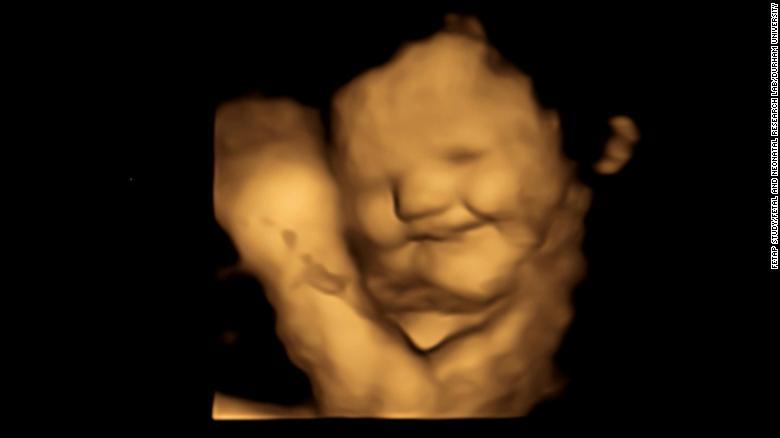

Зародишите в утробата се усмихват, когато бъдат изложени на вкуса на морковите, консумирани от техните майки, и се мръщят на къдравото зеле (кейл). Това сочи изследване, публикувано в сряда в Psychological Science.

Зародиш, изложен на вкуса на къдраво зеле.

20 минути, след като изяждат капсулите, жените са подложени на 4D ултразвук, като крайния резултат е съпоставен с 2D изображения на зародишите.

Оказва се, че вероятността зародишът да е направил гримаса, сходна с тази на усмивка, е много по-висока в групата, консумирала моркови. Същевременно при тази с къдраво зеле повечето зародиши са направили физиономия, наподобяваща мръщене или плачещо личице.